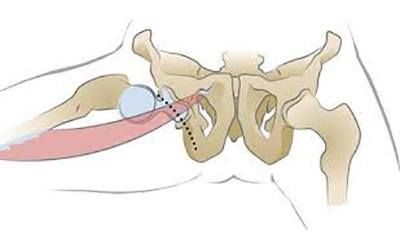

Здоровье суставов: Трохантерит и его влияние на мышцы